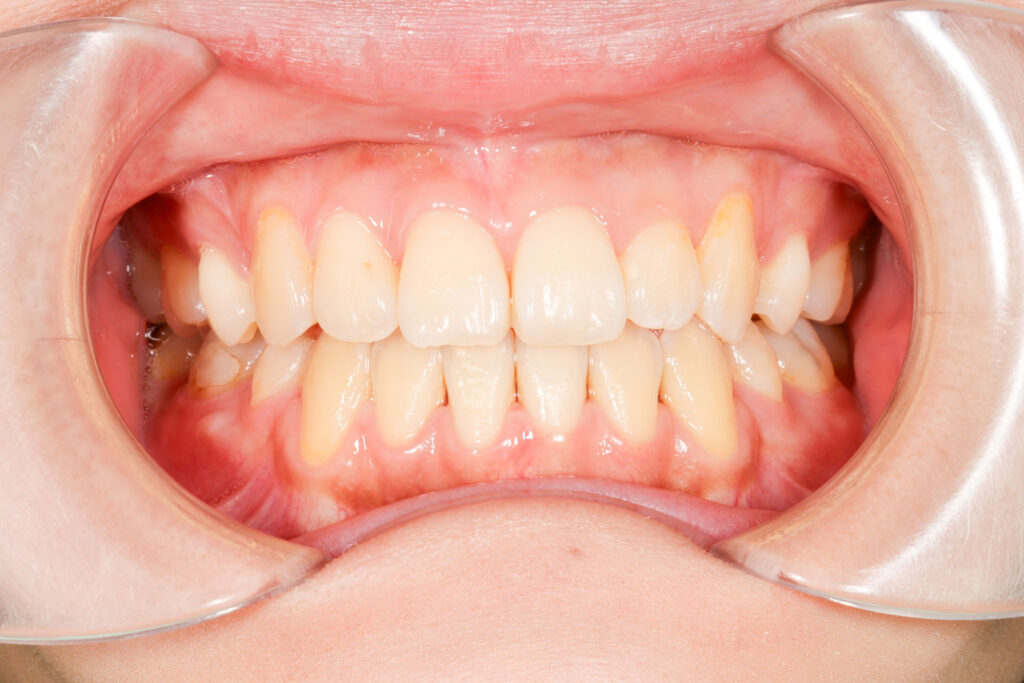

Before

After

年齢 10代

治療装置 表側の矯正装置(ホワイトコース)

治療内容 上下左右4本抜歯

治療期間 2年1か月

リスク 歯の移動に伴う痛み、歯肉退縮、歯根吸収、歯肉炎、虫歯

主訴 ガタガタが気になる

症状 叢生(ガタガタ)

治療回数 25回程度

総額費用 105万円程度